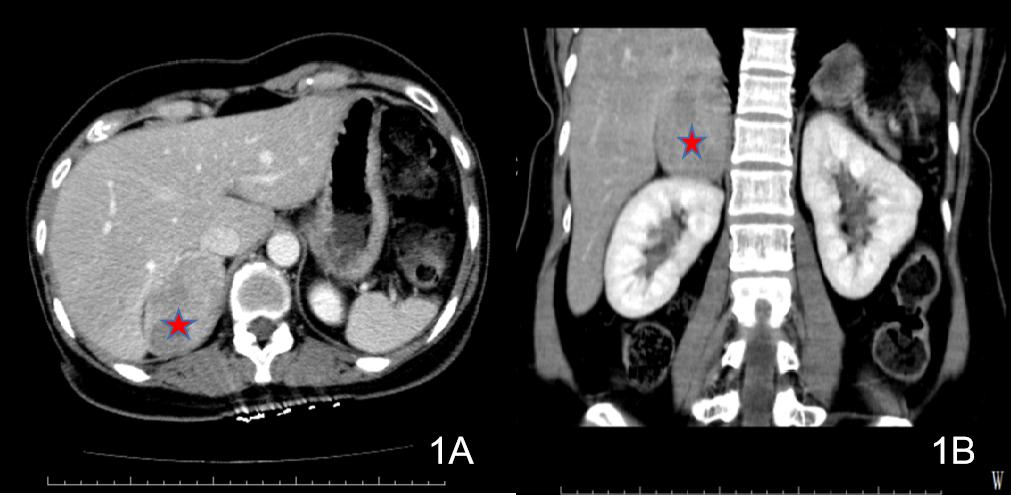

诊治经过如下。入院后查:HGB 81 g/L;生化十项(住院):CR 123.1 μmol/L,GLUC 22.22 mmol/L;心肌损伤标志物:TnI >50.0 ng/mL,MYO 377.45 ng/mL,CKMB Ⅱ 80.86 ng/mL;血气分析:pH 7.361,PCO2 33.5 mmHg,PO2 144.0 mmHg,BEb −5.0 mmol/L。予吸氧、积极补液扩容及输注悬浮红细胞(6U)、控制血糖等治疗。2021-06-18凌晨复查CT提示“左侧肾上腺区占位范围较前相仿,腹腔内积液较前增多”(见图 3)。2021-06-18早上复查BCA示Hb回升至115 g/L。

图 3 2021-06-18患者2腹部CT(腹腔积液较前增多)